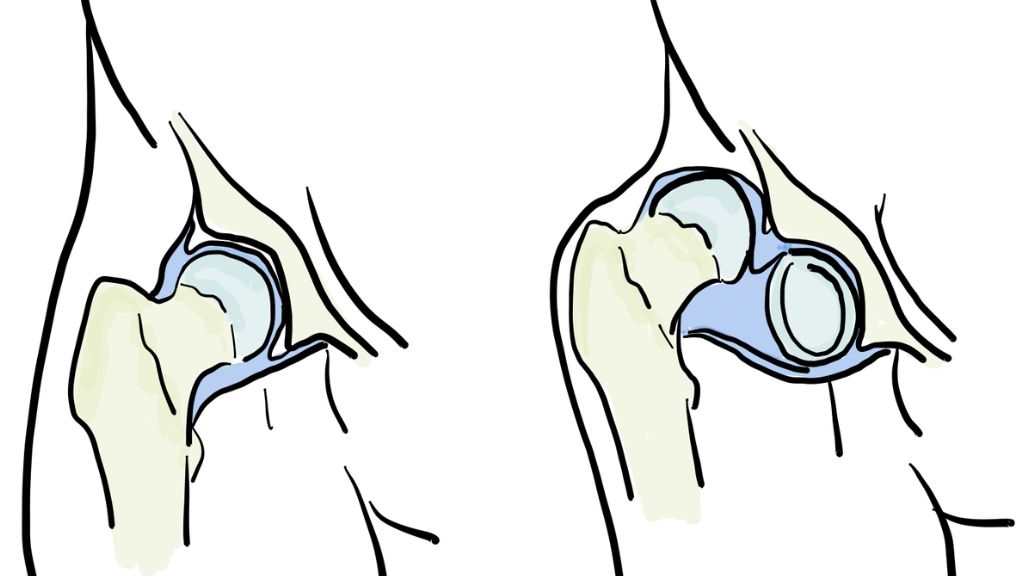

Bẩm sinh trật khớp háng (CHD) là tình trạng trẻ sinh ra với khớp háng không ổn định do cấu trúc khớp phát triển bất thường ngay từ giai đoạn bào thai. Bệnh còn được gọi là loạn sản khớp háng phát triển. Khi trẻ lớn lên, mức độ lỏng lẻo của khớp có thể tăng dần.

Trong tình trạng này, chỏm xương đùi có thể trượt ra khỏi ổ cối, thậm chí bị lệch hoàn toàn khi vận động. Theo các nghiên cứu, có khoảng 1/1000 trẻ sơ sinh bị trật khớp háng ngay từ lúc chào đời.

Việc sàng lọc được tiến hành ngay khi trẻ chào đời và tiếp tục trong năm đầu tiên. Phương pháp thường dùng nhất là khám lâm sàng. Bác sĩ sẽ nhẹ nhàng xoay và di chuyển khớp háng của trẻ để tìm dấu hiệu lục cục, đây là âm thanh hoặc cảm giác cho thấy khớp bị trật. Hai động tác kiểm tra chính gồm:

- Nghiệm pháp Ortolani: Bác sĩ đẩy nhẹ đùi lên và dang ra ngoài (dạng) để xem phần chỏm xương đùi có trượt vào ổ khớp hay không.

- Nghiệm pháp Barlow: Bác sĩ đưa đùi vào trong (khép) đồng thời đẩy nhẹ xuống để xem khớp có dễ bị trật ra ngoài không.